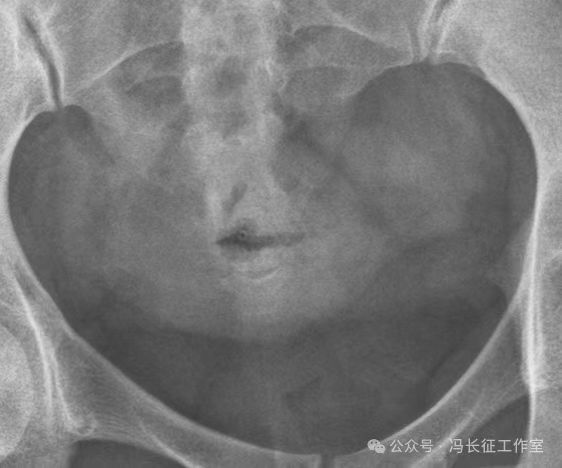

下面是一例正常子宫输卵管造影图(4张片)

微信图片_20240215160222.jpg